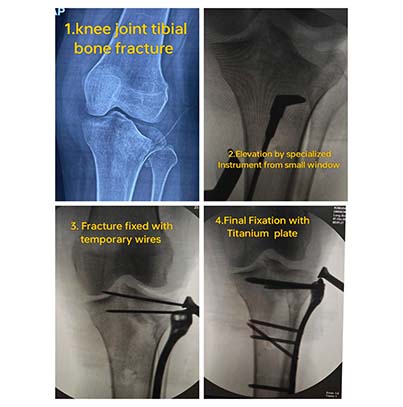

For fractures that are displaced, complex, or unstable, surgical fixation becomes essential to restore normal anatomy and function. Through ORIF, I make a precise incision, realign the bone fragments accurately, and secure them using plates, screws, pins, or specialised orthopaedic implants. This method ensures stable fixation, quicker recovery, and long-term joint preservation, especially in fractures involving the hip, shoulder, elbow, wrist, or ankle. Every surgical plan is tailored to the patient’s age, bone strength, and lifestyle demands.

I follow minimally invasive techniques whenever possible, reducing surgical trauma, minimizing scarring, and promoting faster healing. My operative approach prioritizes safety, precision, and early mobilization so patients can return to their routine confidently. With my extensive fracture fixation experience, I ensure that surgical treatment is done with absolute accuracy to prevent complications such as malunion or stiffness.